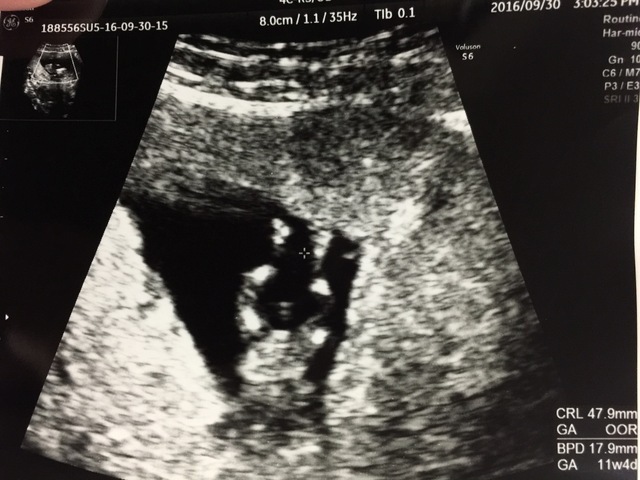

11週0日(11w0d・性別不明)|kiki34 さん(28歳)

エコー写真撮影時のエピソード:

両親や姉妹に報告するときにエコーの写真を見せました。とても喜んでもらえました。 毎回のエコー写真はアルバムにしてコメントをつけて保存するようにしています。

だんだん大きくなっているのが目に見えてわかりコメントを書くことによってその時の気持ちがわかるようになるので見返してて楽しいです。将来は産まれてきた我が子にあげる予定です!